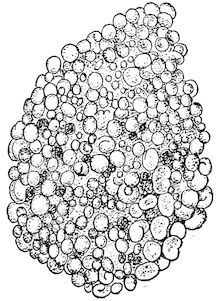

Fig. 8.—Transverse section through the middle region of the face in a pig suffering from osseous cachexia.

18In the final stages, the bones may be cut with a knife, and a time arrives when bony tissue seems completely to have disappeared; thus, as shown in Fig. 8 herewith, it was possible to cut the entire head of a pig into thin slices without the slightest difficulty. All parts of the head had been affected by the softening change.

From the chemical point of view, the diminution in mineral salts and in phosphate of calcium has long been recognised, but the degree of this change varies according to the phase. In human beings the proportions have been estimated as follows: Normal bone, 50 to 80 per cent. of phosphate of calcium; bone in persons suffering from osteomalacia, 5 to 20 per cent. of phosphate of calcium. The changes in the ossein have not been carefully studied. We only know that histologically the ossein becomes fibrillar, and that chemically it no longer retains its normal composition.